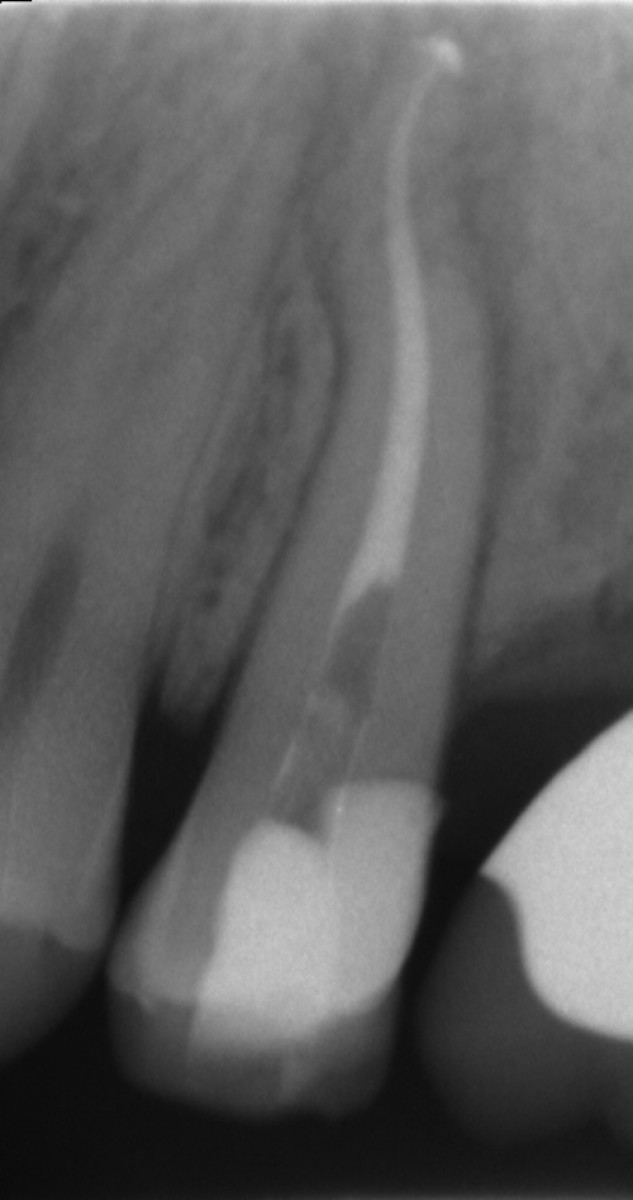

54 ys old male patient came with the complaint of pain and sensitivity in mandibular right first molar and endo-treatment was advised.

After accessing the pulp chamber and locating all the canal orifices, patency to length is confirmed with a stainless-steel manual file (0.10-0.15) and the Hyflex file sequence is selected in relation to the anatomical challenge encountered during manual scouting and the analysis of the preoperative x-ray  showed a complex and highly curved anatomy of the roots. The canal orifices were relocated using the Orifice Opener EDM In this case a 15.3 and a 20.5 were used to create a smooth mechanical glide path thanks to the great flexibility and cutting efficiency of the file. The distal canal was completed with the OneFile while in the palatal and mesio-buccal was not possible to reach WL with 25.8 EDM because of the curvature. Thus the sequence was completed with 25.4, 30.4, 35.4 from cm files sequence and 40.4 EDM file in both canals, according to the apical diameter gouging. Cold 5 % sodium hypochlorite was used throughout the procedure as the irrigant. Canals were dried with paper point and obturation was done by using single cones of taper and size corresponding to the ones of the last file used for shaping plus Gutta Flow Bioseal as cement. The tooth was restored with a composite overlay (figure 6,7).